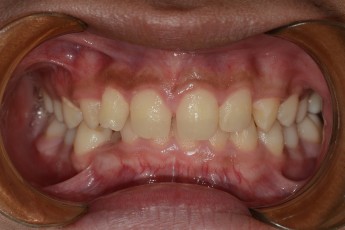

Before

After